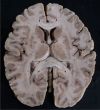

NEUROANATOMY I. - Structures of the CNS

Telencephalon; Cerebrum

White mater of telencephalon

Commissural fibers of thelencephalon